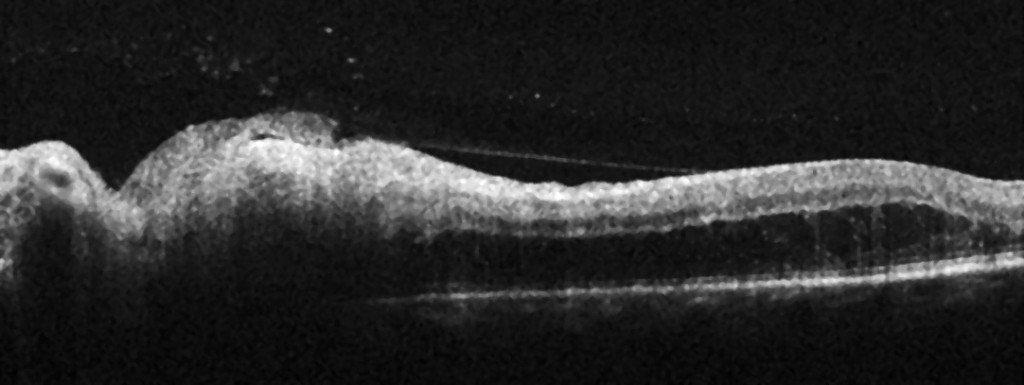

Optical coherence tomography (OCT) of the left optic disc showed thickening of the peripapillary retinal nerve fibre layer with an average thickness of 159 µm (> 95 % reference range) (Figure 2). A thickening of the inner retinal layers was also seen, corresponding to the temporal infiltrate.

The retrobulbar pain disappeared after a few days. After a week of treatment, the patient also experienced some improvement in vision, and her best corrected visual acuity was 0.8. On examination, there were still some cells in the vitreous, but the temporal peripapillary infiltrate was slightly smaller and more sharply defined. A second intravitreal injection of clindamycin was administered. After another week of treatment, best corrected visual acuity was 1.0. The infiltrate had become even smaller, and OCT showed normalisation of the peripapillary retinal nerve fibre layer, with an average thickness of 118 µm (within the 95 % reference range). The patient received a third and final intravitreal injection of clindamycin.